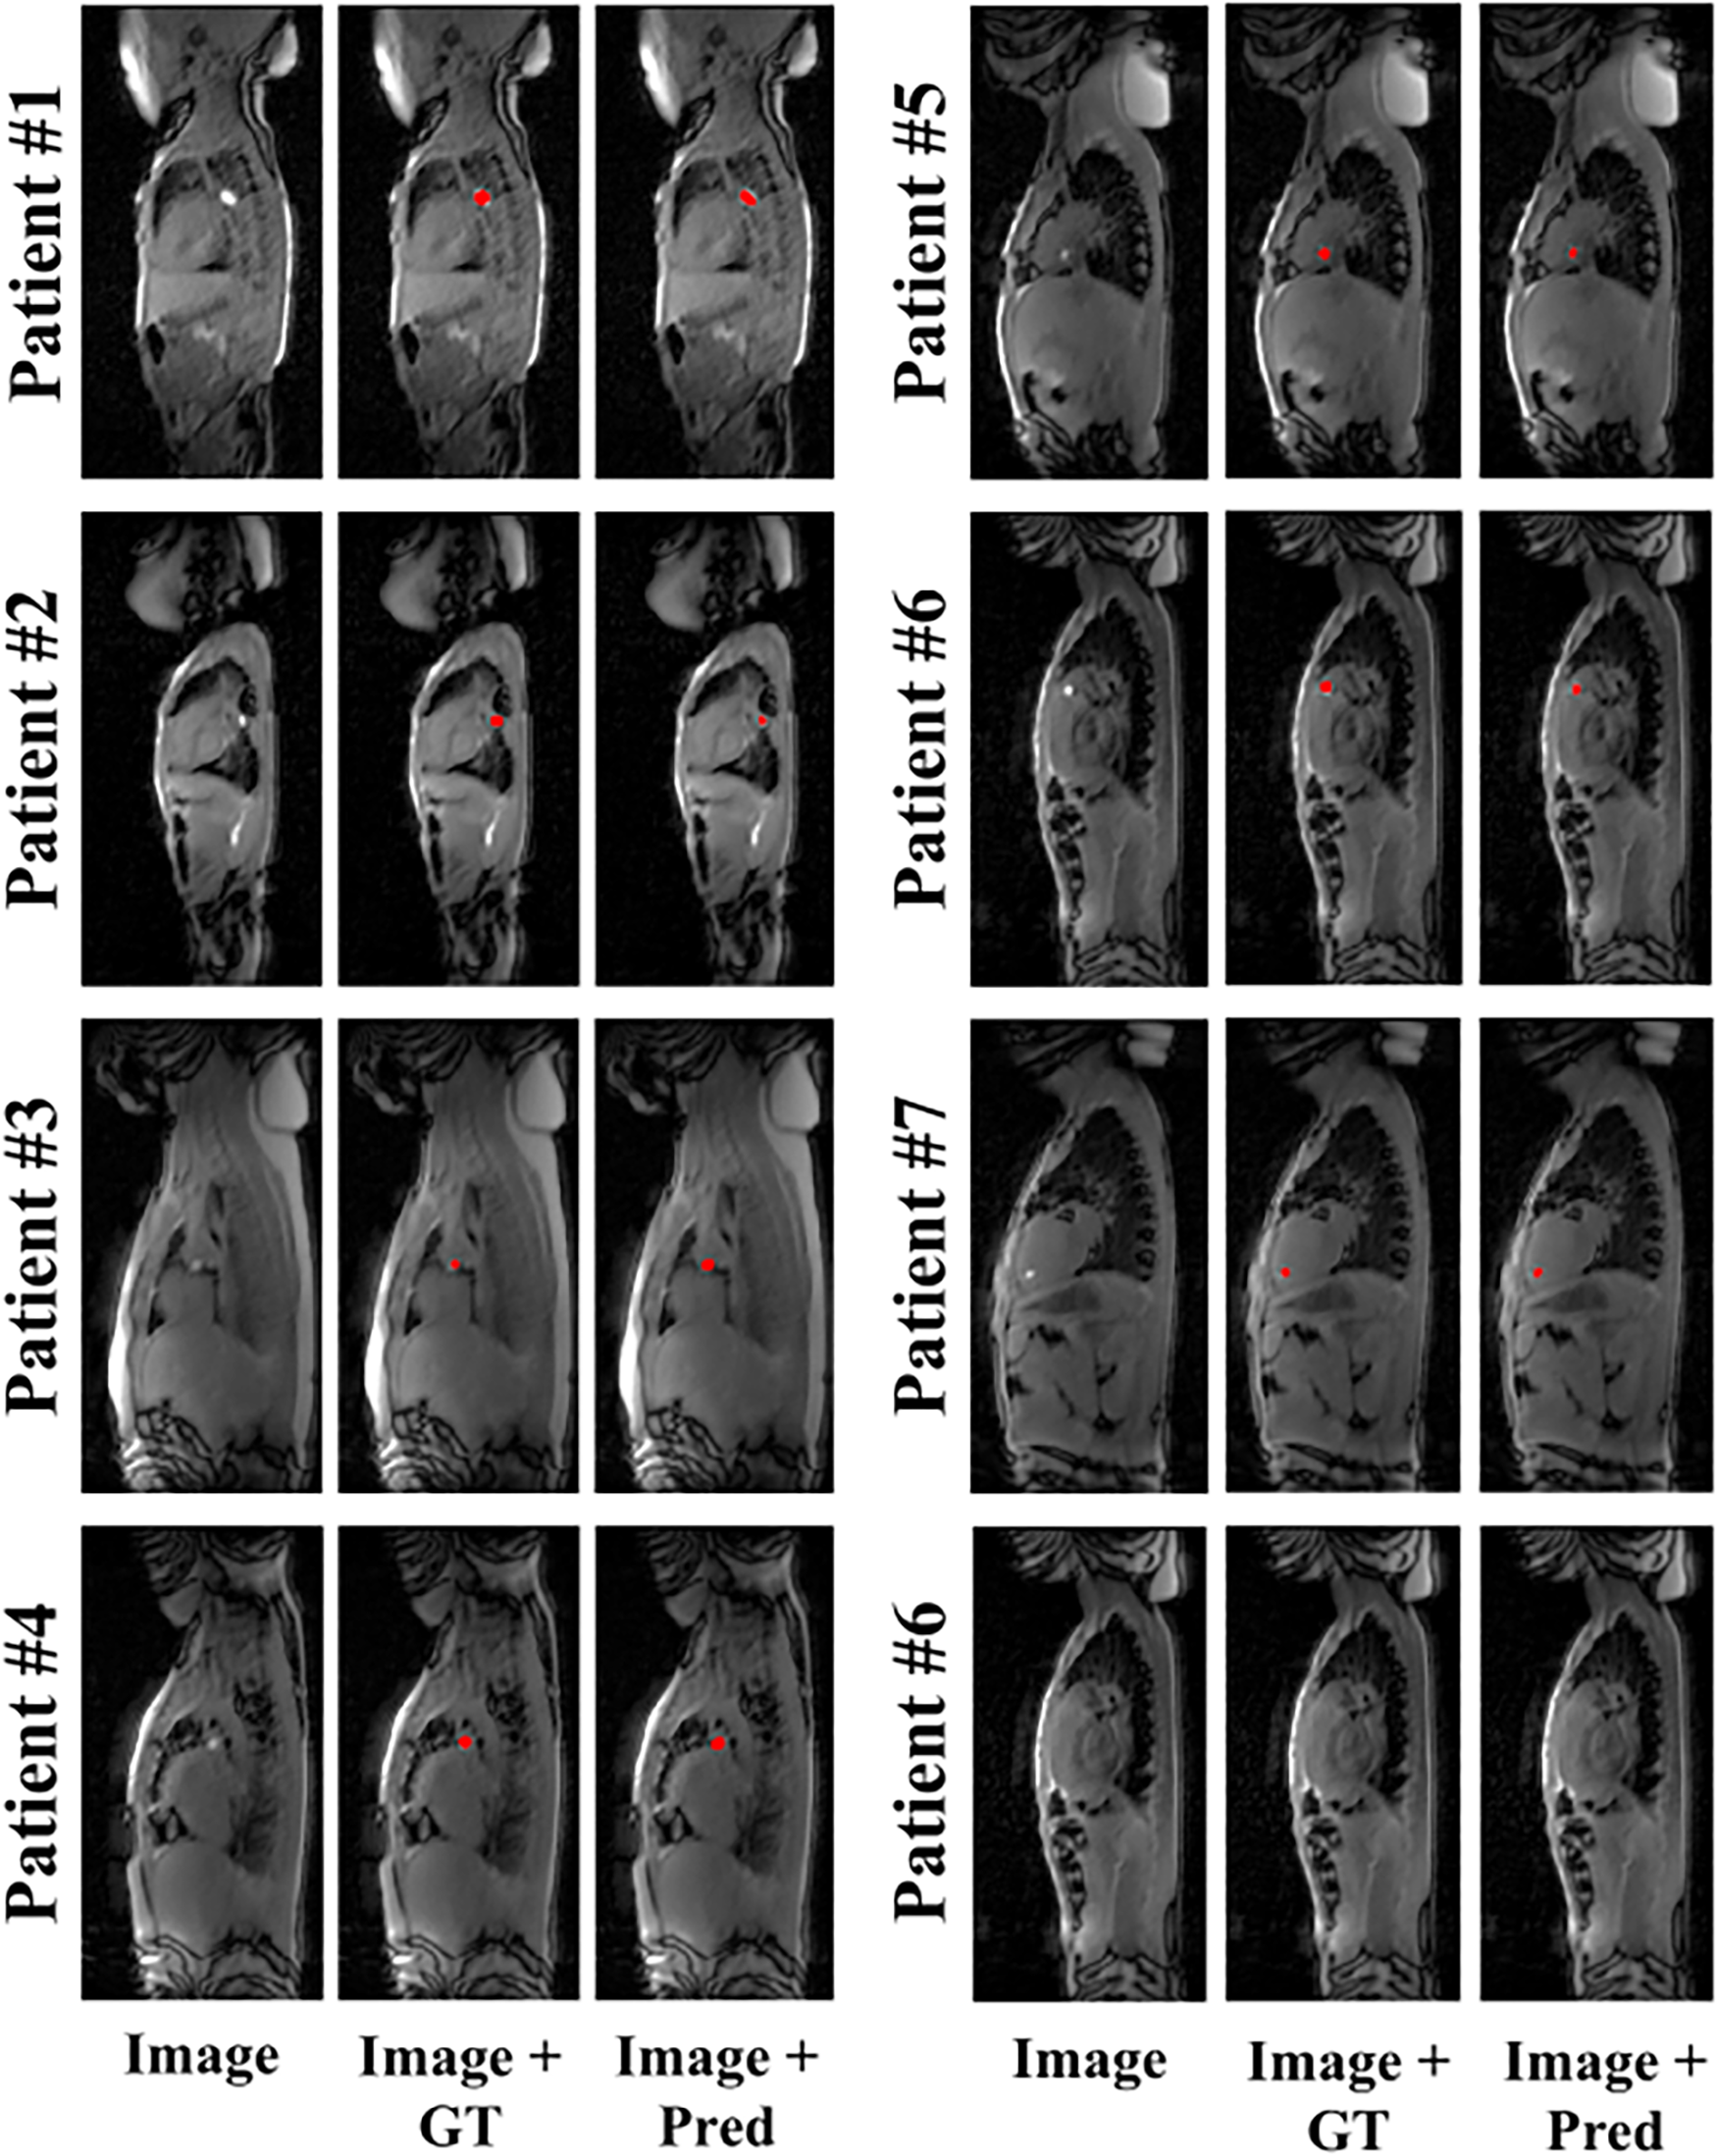

Representative example predictions of the network alone, for each of the seven patients who underwent MRI-guided cardiac catheterization, are shown in Figure 2. A large variation of catheter-to-blood contrast, catheter balloon size/shape, and overall anatomy can be observed within this patient cohort. Despite these variations, accurate prediction of the catheter balloon was achieved in all subjects using the proposed network. One representative example of true negative detection is also shown (see the bottom right case in Figure 2). No catheter was present in any part of this image. Interestingly, despite the presence of hyper-intense signal, specifically from fatty tissue, the network was able to predict the absence of the catheter balloon. On an image basis, the mean accuracy, sensitivity and specificity of the network alone over all patients were 87.5 ± 10.9%, 93.4 ± 13.8% and 85.3 ± 13.8%, respectively.

Figure 2

Representative example predictions of the network for all patients who underwent MRI-guided cardiac catheterization. Image (input to the network), ground truth (GT) segmentation masks overlaid onto the input image (i.e., Image + GT) and network prediction masks (Pred) overlaid onto the input images (i.e., Image + Pred) are shown for each subject. Accurate catheter segmentation was achieved for each of the seven patients. An additional true negative example (patient #6) is provided (bottom right).